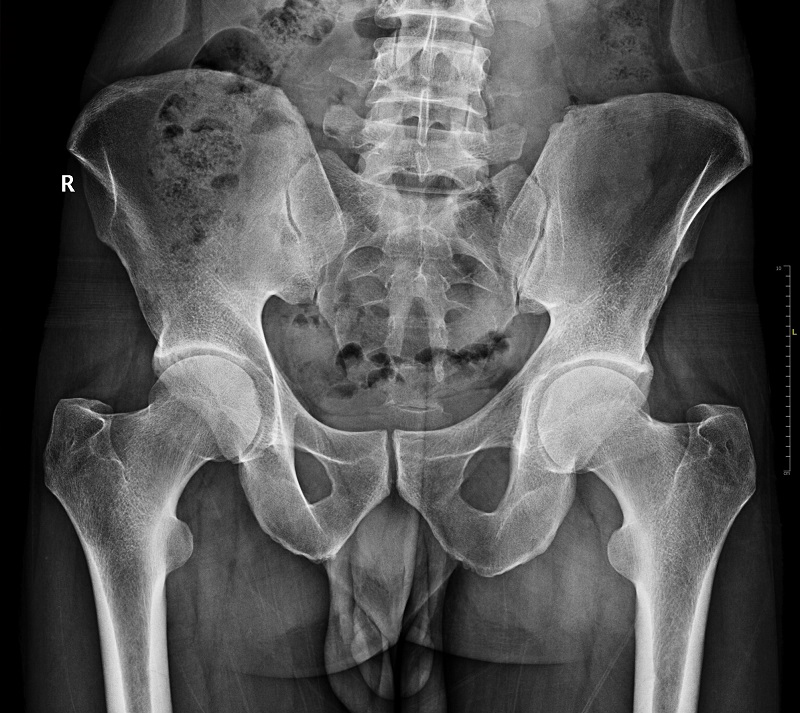

Radyografi

Direkt radyografi iskelet sistemine ait patolojik değişikliklerin tanımlanması ve tedavi takibinde en çok kullanılan temel tanı yöntemidir İskelet sisteminde direkt grafi kırıkların değerlendirilmesi, yapısal (skolyoz gibi) ve doğumsal değişiklikler, ortopedik implantların değerlendirilmesi, kemik iltihapları, eklemlerin dejeneratif ve iltihabi hastalıkları, kemik tümörleri ve metabolik kemik hastalıklarının tanısında kullanılır.

Radyografi iskelet sistemine ait patolojik değişikliklerin tanısında en çok kullanılan temel tanı yöntemidir.